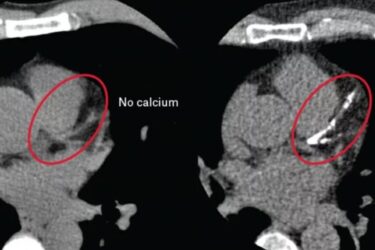

Are Cardiac Calcium CT Scans Useful?

My doctor recently recommended that I get a cardiac CT calcium scan to help stratify my risk of cardiovascular disease (CVD). So of course I was interested in how good this scan is, because diagnostic tests to assess risk, especially in those who are asymptomatic, can be tricky. I was happy to discover that the short answer is – yes. These tests...